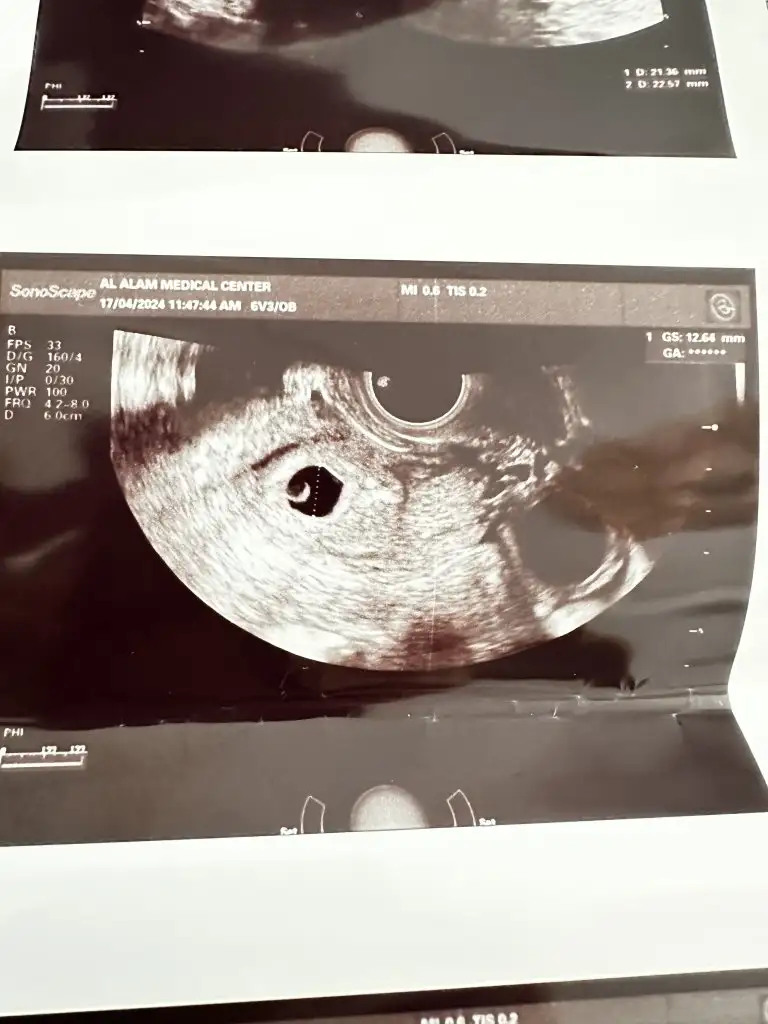

Merhaba bebegi gorup kalp atisini diymaniza cok sevindim. Adetiniz kac gun gectikten sonra gordunuz bebeginizi. Benim adet gunumun gecmesinin 13.gunu 6 haftalik gorunuyor kesem 12mm olmus yolk var ama icinde bebek yok.. yardim eder misiniz sizinde oyle miydi? Saglikla bebginizi kucaginiza almanizi diliyorum. 💜

Ben 6.haftada hamile olduğumu öğrendim. Beta hcg 19.000 bindi. Hemen doktora gittik, keseyi gördük. 9 mmdi.

6+6 da kontrole gittim kese 25 mm olmuş. Hcg değerim de 37.000 olmuş. Ama bebek ve kalp atışı yok. Ultrasonda kese fotoğraftaki gibi gorunuyor.

Kesede ufak bir şey gorunuyor ama doktor bişey demedi. Haftaya tekrar bakacağız dedi. Sizce burada bir şey var mı? Benimle benzer durumu yaşayıp bebeği sonra gören var mı? Boş gebelik olmasından dolayı endişe duydum. Hcg değerlerim normal mi?, Hani Öncelikle geçmiş olsun Ben de aynı durumdayım ama ben doktora gitmedim işte bu ayın değil de diğer ayın 7'sinde randevu aldım gideceğim Evde beklemeyi tercih ettim Bir de bir şey soracağım peki Yani bir belirti var mı lekelenme işte karnında kıpırtı falan var mı